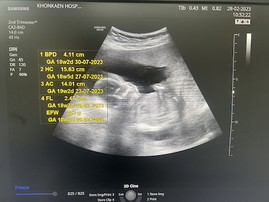

ซาวตอน 18 สัปดาห์ค่ะ ลุงหมอบอกผมเป็น ผุ้ชาย

คล้ายๆ กันเลยค่ะแม่ ลูกเรา 18w แล้ว